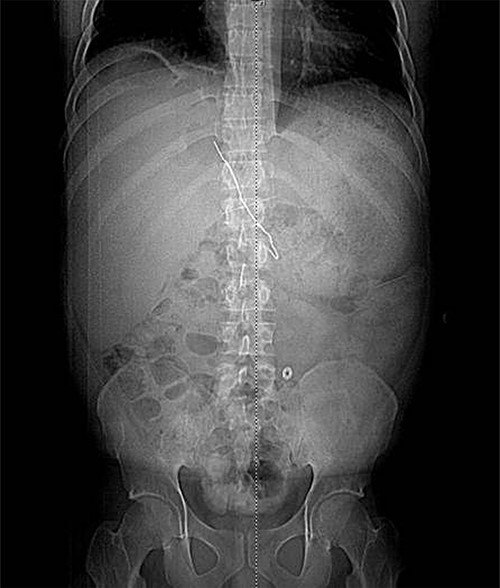

The patient presented after ingestion of an open paperclip and insertion of a sewing needle into his ventral hernia ~4 months prior. He presented with fever, tachycardia and abdominal pain, but a benign abdominal exam, noting only mild tenderness over his large, reducible ventral hernia. A computed tomography (CT) of the abdomen and pelvis showed a 10-cm metallic foreign body extending from the mid transverse colon to the left hepatic lobe with an intrahepatic abscess measuring 9.1 x 7.3 cm (Figs 1–3). In addition, there were two other metallic foreign bodies: one extraluminal in the left upper quadrant, which was stable from prior imaging, and a subcutaneous foreign body above the hernia contents. Blood cultures grew streptococcus intermedius and he was started on broad spectrum antibiotics (piperacillin–tazobactam). The case was discussed with Interventional Radiology (IR) and deemed reasonable for attempt at percutaneous abscess drainage and trans-hepatic foreign body retrieval.